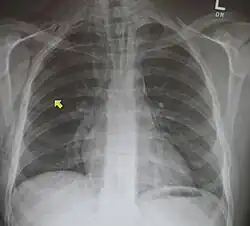

Pneumomediastino (do grego pneuma ar) ou enfisema mediastinal é uma presença anormal de ar entre os pulmões (no mediastino). Descrito pela primeira vez em 1819 por René Laennec.[1] A condição pode resultar de trauma físico ou outra lesão que cause que ruptura das vias respiratórias (como tráquea, laringe ou pulmões) ou da via digestiva (como esôfago e estômago) para a cavidade torácica.